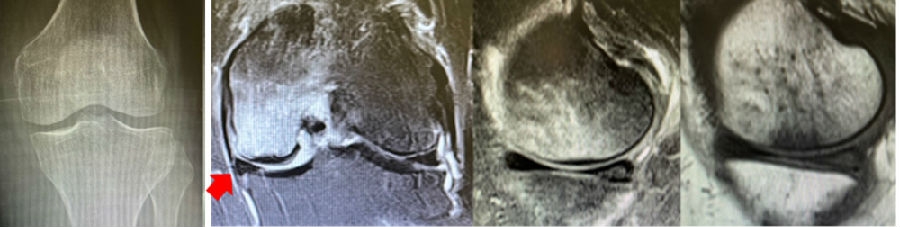

病例:女,65岁,主诉左膝关节内侧疼痛2月余。2017年11月X光未见左膝骨质异常。MR见股骨内侧髁骨坏死,半月板相对突出百分比(RPE)28.3%,合并内侧半月板后根部撕裂,矢状位病变区域前后径为11.67mm,关节线会聚角2.68°

予消炎止痛药物口服、静滴唑来膦酸钠注射液,避免负重6周,后改部分负重,12周后全负重。

2018年2月复查MR见骨髓水肿明显吸收,坏死灶边界清晰,半月板相对突出百分比(RPE)28.92%

2018年6月复查MR见骨髓水肿基本完全吸收,坏死区修复良好,半月板相对突出百分比(RPE)38.54%,患者临床症状消失。

提示坏死好转了,但半月板突出进展了,膝关节的退变加重了。